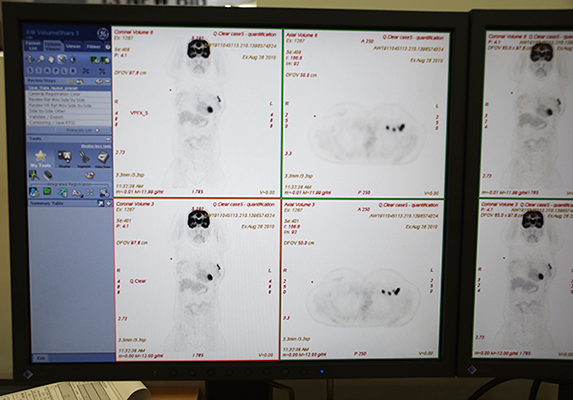

核医学装置関連では,PET/CT「Discovery PET/CT 610(128slice)」と「Discovery PET/CT 710(128slice)」に搭載される最新アプリケーションQ.Clearやβアミロイド検出用薬剤の国内展開を紹介した。

Q.Clearは,PET/CTの課題であった定量性のばらつきを向上させる技術。逐次近似再構成の演算処理を行う際に,繰り返し演算を行ってもノイズが増幅しないよう,ノイズをコントロールする演算式をアルゴリズムに組み込んだ。その結果,SUV定量値の精度が上がるとともに,画質も改善され微小な病変も描出できるようになる。安定した定量性を確保したことで,がん診療における治療効果判定に用いることができる。

定量精度と画質向上を両立したQ.Clearの画像(下段)